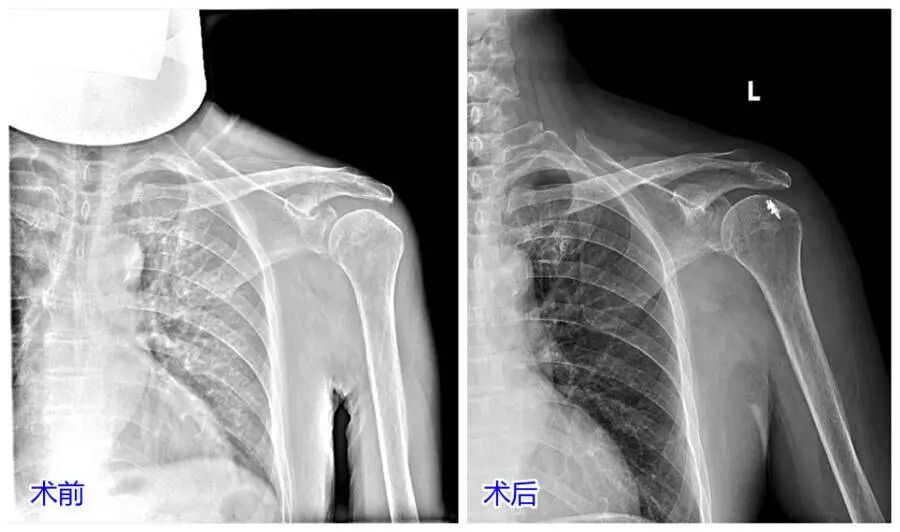

本月初我们科室接诊了一位患者,以夜间疼痛为重,肩关节活动范围明显减少,活动受限1年余,一直保守治疗,效果不佳,左肩部及活动受限现象无好转。来到我们科后,诊断为左侧肩袖损伤,合并左侧肩关节冻结肩,这种情况如果继续保守治疗是没什么效果的,而且时间长了,病情会更加严重。

手术团队很快为她安排了左肩关节镜下探查、清理+肩峰成型术+肩袖撕裂修复术,手术效果明显,再通过个性化的康复锻炼,一般均会很快康复。我们每个月都会接诊不少肩袖损伤的患者,60岁以上比较常见,经过肩关节镜微创治疗后,效果都很不错。